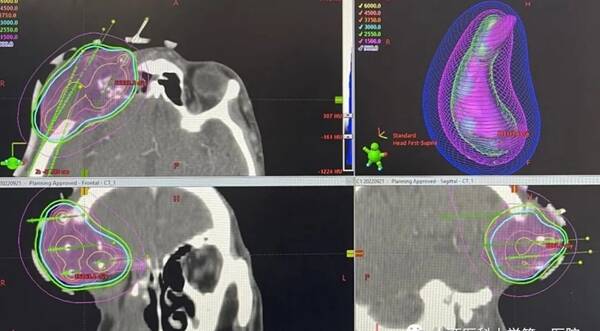

△完美的劑量分布

如何攻克復(fù)發(fā)轉(zhuǎn)移頭頸部腫瘤是臨床面臨的一大難題,醫(yī)學(xué)指南推薦的首選方案是化療聯(lián)合靶向免疫等全身系統(tǒng)治療,但是療效不佳,平均緩解時(shí)間僅為5個(gè)多月。山西醫(yī)科大學(xué)第一醫(yī)院放療科在2019年下半年引進(jìn)了國際先進(jìn)的三維后裝治療儀,在宮頸癌根治性放療中療效顯著,治愈率高,副作用小,深受患者和醫(yī)生的歡迎。為了應(yīng)對(duì)復(fù)發(fā)轉(zhuǎn)移頭頸部腫瘤,在主任李險(xiǎn)峰的支持下,侯彥杰副主任醫(yī)師大膽創(chuàng)意,與物理師/技師/護(hù)師團(tuán)隊(duì)密切配合,于9月21日為一名手術(shù)后放療后復(fù)發(fā)再次術(shù)后二次復(fù)發(fā)的頭頸部腫瘤(翼腭窩區(qū))患者完成高難度后裝近距離插植治療。術(shù)前基于該患者CT圖像制定插植計(jì)劃,并同時(shí)制定了個(gè)性化3D打印多通道非共面模板,在模版的輔助下手術(shù)過程非常順利,30分鐘內(nèi)完成了5根插植針的置入,術(shù)前術(shù)后放療計(jì)劃吻合,單次給予患者30Gy的放療劑量,達(dá)到精準(zhǔn)近距離治療的目的。

切除翼腭窩區(qū)腫瘤屬于高難度手術(shù),而術(shù)后放療后的二次手術(shù)及再程放療則更能體現(xiàn)一個(gè)三甲醫(yī)院的水平和擔(dān)當(dāng)。本例患者的治療經(jīng)過展示了山西醫(yī)科大學(xué)第一醫(yī)院腫瘤治療中多學(xué)科間的密切合作,而本次3D打印非共面模版引導(dǎo)下的插植放療更是達(dá)到了“錦上添花”的效果。

李險(xiǎn)峰主任介紹,山西醫(yī)科大學(xué)第一醫(yī)院是省內(nèi)率先開展三維后裝近距離治療的單位,同時(shí)也是第一家開展近距離插植治療的科室,目前已完成13例插植治療,均達(dá)到預(yù)期治療效果,而本例患者的3D打印非共面模版引導(dǎo)下的插植放療更是將近距離治療的精髓發(fā)揮到了極致,是數(shù)字醫(yī)學(xué)、解剖學(xué)和劑量學(xué)的完美融合,在省內(nèi)屬首例,該區(qū)域的插植治療在全國都無相關(guān)報(bào)道。